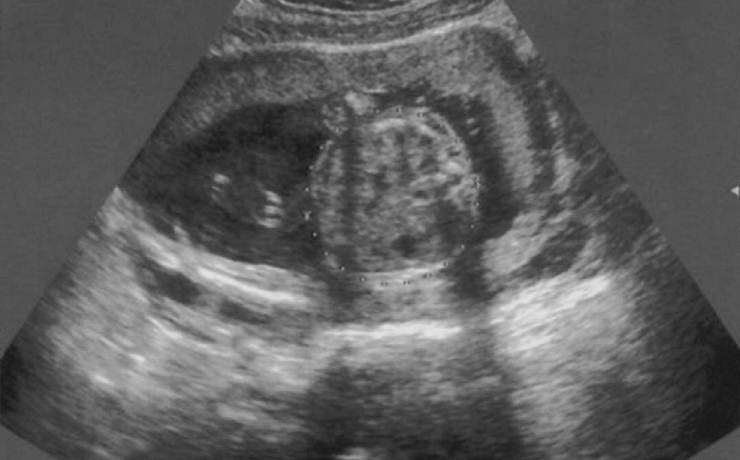

La vesícula biliar es una bolsa de 7 a 10cm de longitud y de 3 a 5 cm de ancho, la cual mantiene en promedio un volumen de 30-50ml; tiene forma piriforme (forma de pera), la cual se divide para su estudio en tres secciones: el fondo, el cuerpo y